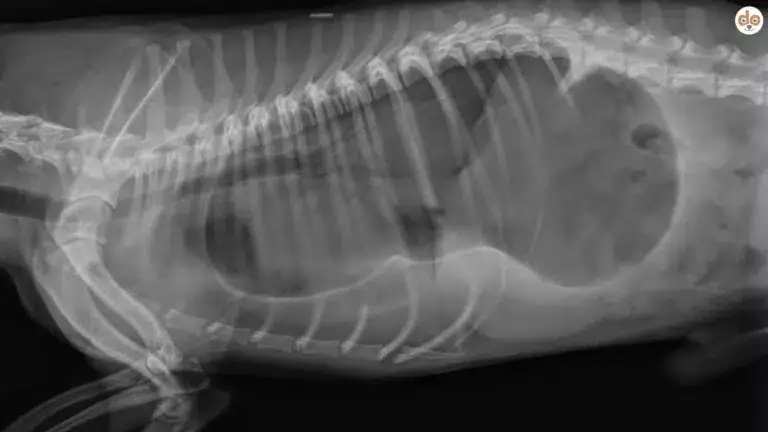

Nach Anamnese und Untersuchung kommen – je nach Fall – Röntgen/Fluoroskopie, Endoskopie, 24-h-pH-Messung/Impedanz, Szintigraphie (Reflux- und Mikroaspirations-Detektion) sowie Therapie-Tests infrage. Wichtig sind Differenzialdiagnosen wie Megaösophagus, Fremdkörper, Gastritis/Pankreatitis oder systemische Erkrankungen.